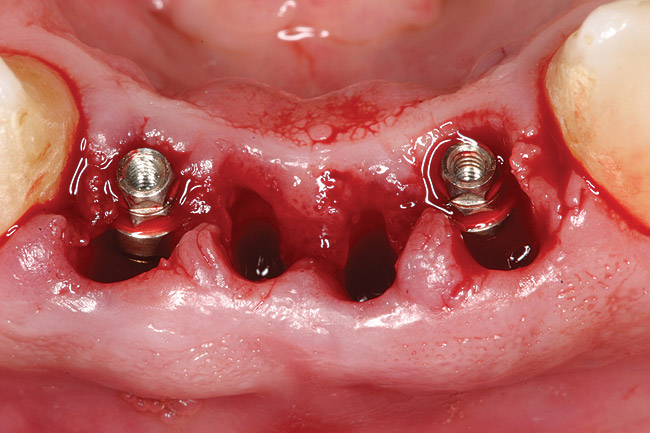

Preoperatively, 1 g of amoxicillin was administered. Using local anesthesia (lidocaine 1:100,000 epinephrine), extractions of teeth No. 23 to No. 26 were performed without raising a flap and with gentle luxation to preserve the remaining facial osseous plate. The sockets were curetted prior to implant placement. A vacuum-formed surgical guide, fabricated based on a diagnostic wax-up of the desired tooth positions for the subsequent fixed prosthesis, was used during implant placement. Osteotomies were performed at sites No. 23 and No. 26 and positioned toward the lingual aspects of the sockets (Figure 3A and Figure 3B). Two tapered implants (OsseoTite™ 313, BIOMET 3i™, Palm Beach Gardens, FL) measuring 3.25 mm x 13 mm were placed. Conical prosthetic abutments (3-mm height) were used to facilitate joining the two implants in a screw-retained fixed partial denture (Figure 4). A laboratory-processed acrylic-resin provisional restoration was altered to allow connection to the temporary cylinders. The provisional was placed into the vacuum-formed surgical guide that was now used to maintain the provisional in the correct 3-dimensional position (Figure 5) while being attached to the temporary cylinders with acrylic resin intraorally. Once a sufficient amount of acrylic resin was placed to secure the cylinders to the provisional, it was removed from the mouth and its contours were completed at the laboratory bench (Figure 6A). The two central incisor sockets were grafted with small-particle allograft material (Puros® Allograft, Zimmer Dental, Carlsbad, CA) to maintain gingival architecture beneath two ovate pontics (Figure 6B). The provisional restoration was inserted and the screws tightened to 20 Nt-cm of torque.

Figure 7a  Stage 1 surgery.

Figure 7a